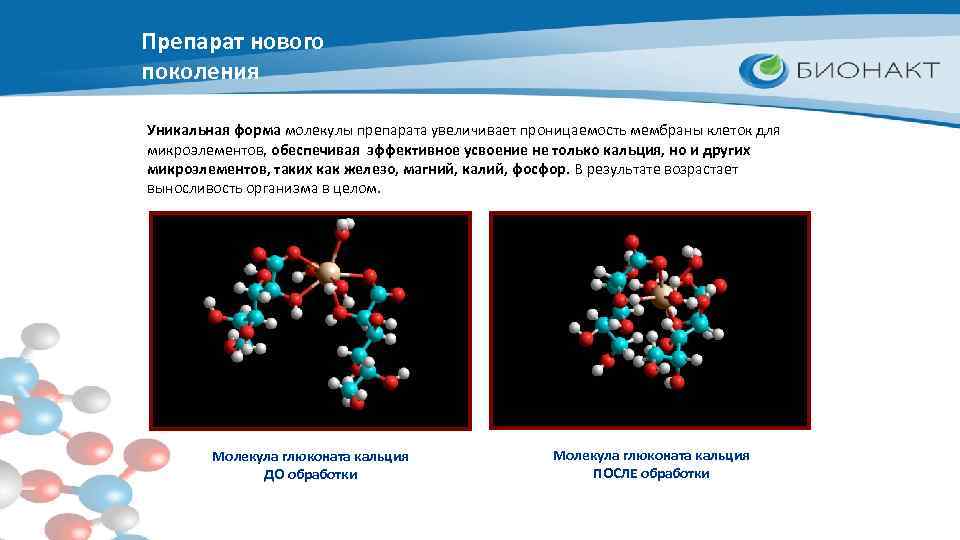

Препарат нового поколения Уникальная форма молекулы препарата увеличивает проницаемость мембраны клеток для микроэлементов, обеспечивая эффективное усвоение не только кальция, но и других микроэлементов, таких как железо, магний, калий, фосфор. В результате возрастает выносливость организма в целом. Молекула глюконата кальция ДО обработки Молекула глюконата кальция ПОСЛЕ обработки

Препарат нового поколения Молекула глюконата кальция ДО обработки Молекула глюконата кальция ПОСЛЕ обработки